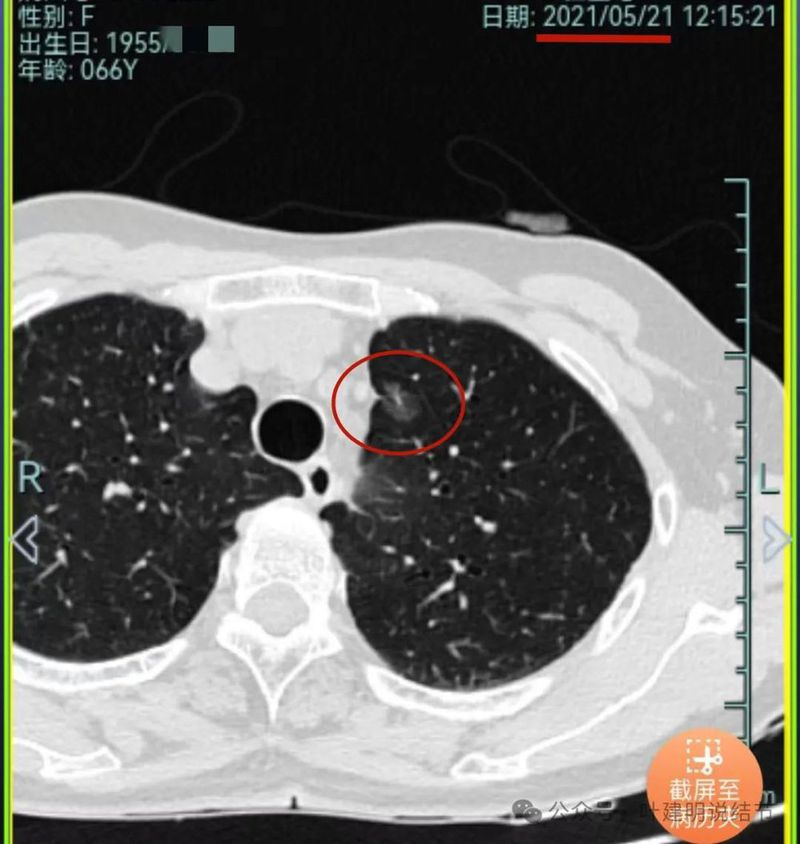

再看2021年随访的影像:

病灶1似乎中间高密度部分略有密度增高。

病灶2与2019年时相仿。

病灶3仍是混合密度,进展不显著。

病灶4仍是伴钙化的,也没有明显进展。

病灶5较前密度略显杂乱,整体密度应该有所增高。

病灶6轮廓较前清楚,灶内有血管穿行,也有轻微胸膜牵拉。

原病灶7已经被切除。